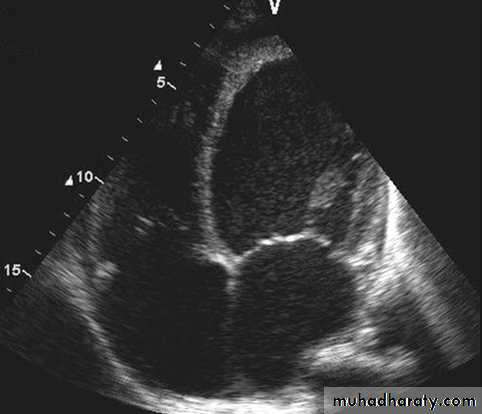

Echocardiogram: Chamber enlargement and global hypokinesis

ECHO

Cardiovascular Diseases